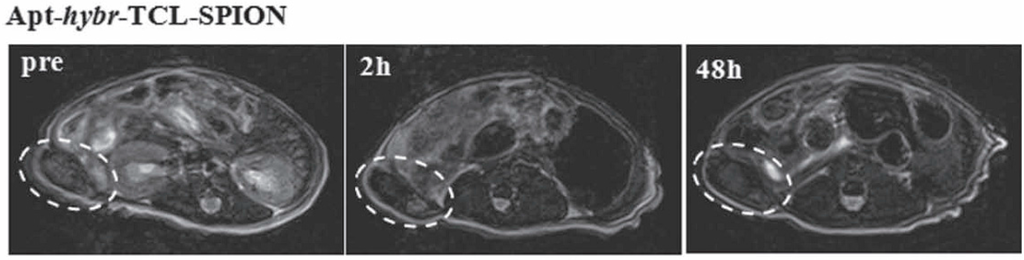

- Yu, M.K.; Kim, D.; Lee, I.H.; So, J.S.; Jeong, Y.Y.; Jon, S. Image-guided prostate cancer therapy using aptamer-functionalized thermally cross-linked superparamagnetic iron oxide nanoparticles. Small 2011, 7, 2241–2249. [Google Scholar] [CrossRef] [PubMed]